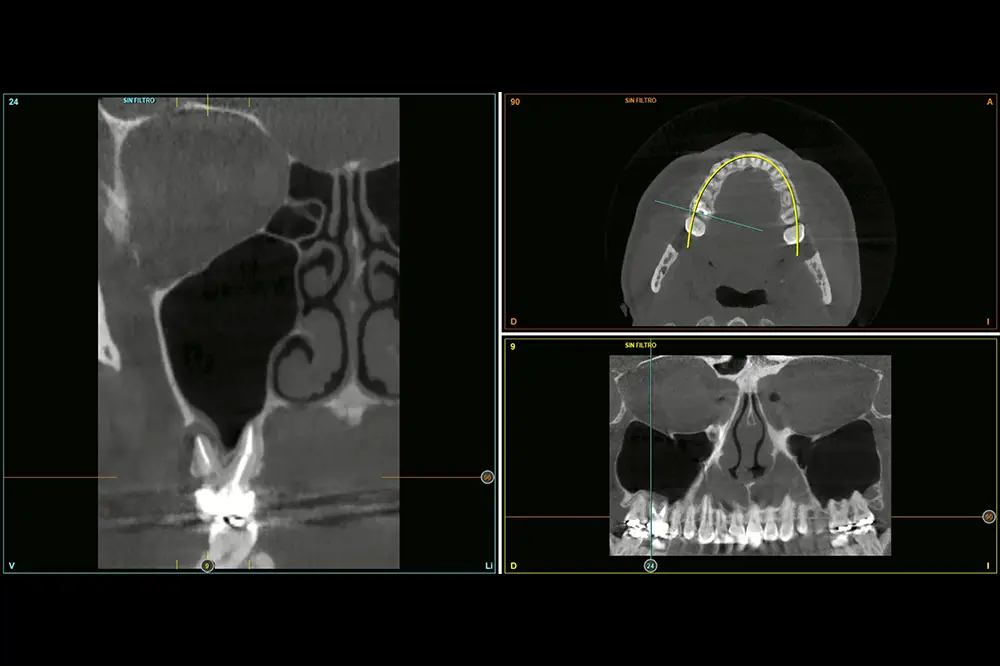

En este caso, la paciente acude con la exodoncia realizada hace dos años de la pieza 16 y una gran atrofia vertical, existiendo únicamente 1 mm en algunas zonas de la cresta, como el área más vestibular, y hasta 3 en la zona más palatina (fig. 9). Procedemos a la realización del fresado tal como se ha descrito en el caso anterior y colocamos el mismo tipo de injerto (autólogo y PRGF- Endoret) y un implante de 4,5 mm de longitud (fig. 10 y 11). Tras la cicatrización a los 4 meses, observamos el aspecto de la zona de la colocación del implante, donde tenemos ahora una altura de 7 mm (fig. 12).

Fig. 9. Cone-beam de planificación donde observamos la escasa altura residual de la cresta a nivel de la pieza 16.